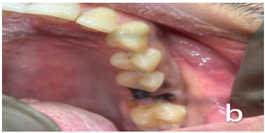

- #26, #36 – Root piece (Figure 2a and 2b)

Figure 2b: Before treatment clinical photograph #26